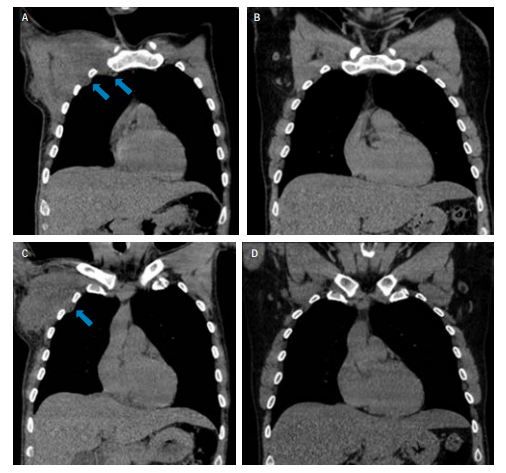

《英国血液病杂志》发表了一则新冠病毒引起霍奇金淋巴瘤缓解的病例:一位被确诊为EBV阳性的经典霍奇金淋巴瘤的61岁男性患者,经评估属于IIIs期(如下方左图)。他因为感染了新冠肺炎,推迟启动抗癌治疗,先治疗新冠。没想到4个月后,PET/CT显示他的淋巴结肿大广泛消退,代谢摄取减少,血液中EB病毒的核酸拷贝数大幅降低。这些情况都说明他的淋巴瘤在感染新冠后获得了缓解(右图)。

左图:刚确诊晚期霍奇金淋巴瘤时的 PET/CT 成像

右图:4 个月后复查的 PET/CT 成像,肿瘤几乎消失